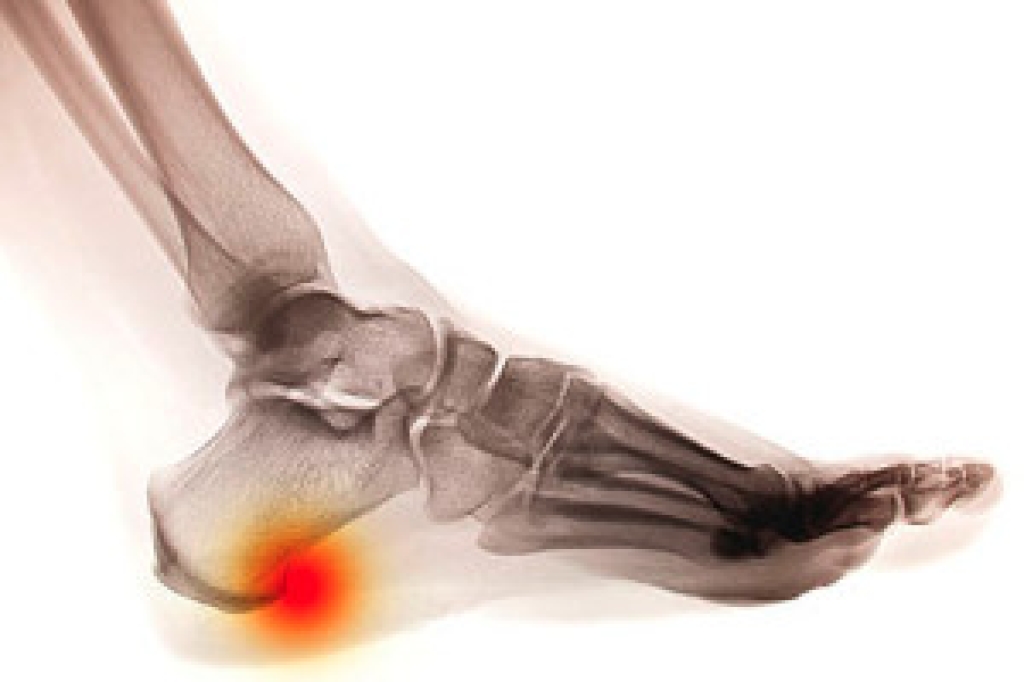

A heel spur is a bony growth that forms on the underside of back of the heel bone, often as a result of repeated stress or strain on the foot. It is commonly associated with plantar fasciitis, a condition that causes inflammation of the tissue along the bottom of the foot. While heel spurs themselves may not always cause pain, they can lead to discomfort when they press against the surrounding tissues. To diagnose a heel spur, a podiatrist will typically begin with a physical examination, assessing the foot for tenderness or swelling. An X-ray is the most common diagnostic tool used to confirm the presence of a heel spur, as it clearly shows the bony growth. If the heel spur is causing pain, relief may be found by practicing stretching exercises, and in some cases, orthotics may be prescribed. If you have developed a heel spur, it is suggested that you contact a podiatrist who can offer the treatment that is best for you.

Heel spurs are formed by calcium deposits on the back of the foot where the heel is. This can also be caused by small fragments of bone breaking off one section of the foot, attaching onto the back of the foot. Heel spurs can also be bone growth on the back of the foot and may grow in the direction of the arch of the foot.